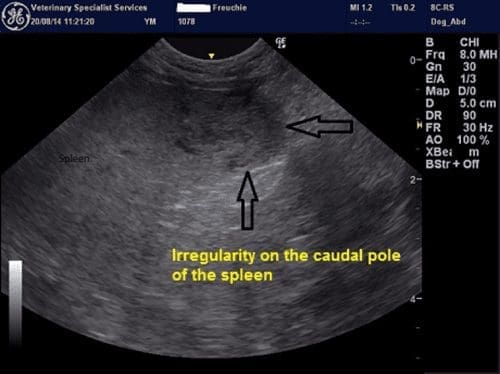

An abdominal ultrasound confirmed the presence of bilateral iliac lymph node enlargement (Approx 1.09 x 1.49cm). FNAs were obtained;. The left and right iliac lymph nodes contained a mixed lymphoid population with frequent plasma cells, eosinophils and macrophages consistent with a reactive change. The caudal pole of the spleen showed some irregularities. The parenchyma here appeared moth-eaten and reticular. Aspirates were obtained and results were consistent with extramedullary haematopoiesis and evidence of inflammation